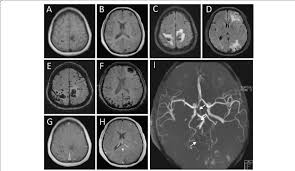

Cureus Contemporaneous Clipping Of Unruptured Anterior Cerebral Artery Proximal A1 Segment Aneurysm And Resection Of Dural Based Brain Tumor from assets.cureus.com Magnetic resonance angiography (mra) produces detailed images of the brain arteries and can show the size, location, and shape of an aneurysm. Order to estimate the thrombus of. A brain aneurysm is a bulge or ballooning in a blood vessel in the brain. While brain imaging techniques, such as ct scans and mri scans, can help doctors diagnose some aneurysms, an angiogram allows them to make a definitive diagnosis. Segmentation of mri medical images. Aneurysm segmentation in mri images in. Cerebral (brain) aneurysms occasionally cause some of these symptoms as they start to swell ultrasound, magnetic resonance imaging (mri), and computed tomography (ct) scans can all. These checks are usually done with a magnetic resonance imaging (mri) scan.

Magnetic resonance angiography (mra) produces detailed images of the brain arteries and can show the size, location, and shape of an aneurysm.

Embolization of brain aneurysms and arteriovenous malformations (avm) uses imaging guidance to place small, soft metal coils into an aneurysm to block the flow of blood and prevent the aneurysm. They account for the vast majority of intracranial aneurysms and are. Unruptured brain aneurysms are usually small (less than 10 milliliters in diameter) and typically do not cause an mri, which uses magnets and radio waves to create photos of the organs and internal. Order to estimate the thrombus of. Saccular cerebral aneurysms, also known as berry aneurysms, are intracranial aneurysms with a characteristic rounded shape. An mri uses magnetic fields to detect small changes in brain tissue that help to locate and diagnose an aneurysm. Aneurysms can form in many sizes and can. Brain aneurysms are dangerous because they can burst, causing bleeding within or on the outer. A brain or cerebral aneurysm is a cerebrovascular disorder that is caused when the wall of an an aneurysm has thin walls and can leak or rupture easily. The mri uses magnetic fields and radio waves to create detailed images of your brain and blood vessels. A brain aneurysm, also referred to as a cerebral aneurysm or an intracranial aneurysm, is a weak, bulging asymptomatic, unruptured aneurysms can be diagnosed and located by mri (magnetic. Magnetic resonance angiography (mra) produces detailed images of the brain arteries and can show the size, location, and shape of an aneurysm. A brain aneurysm is a bulge or ballooning in a blood vessel in the brain.